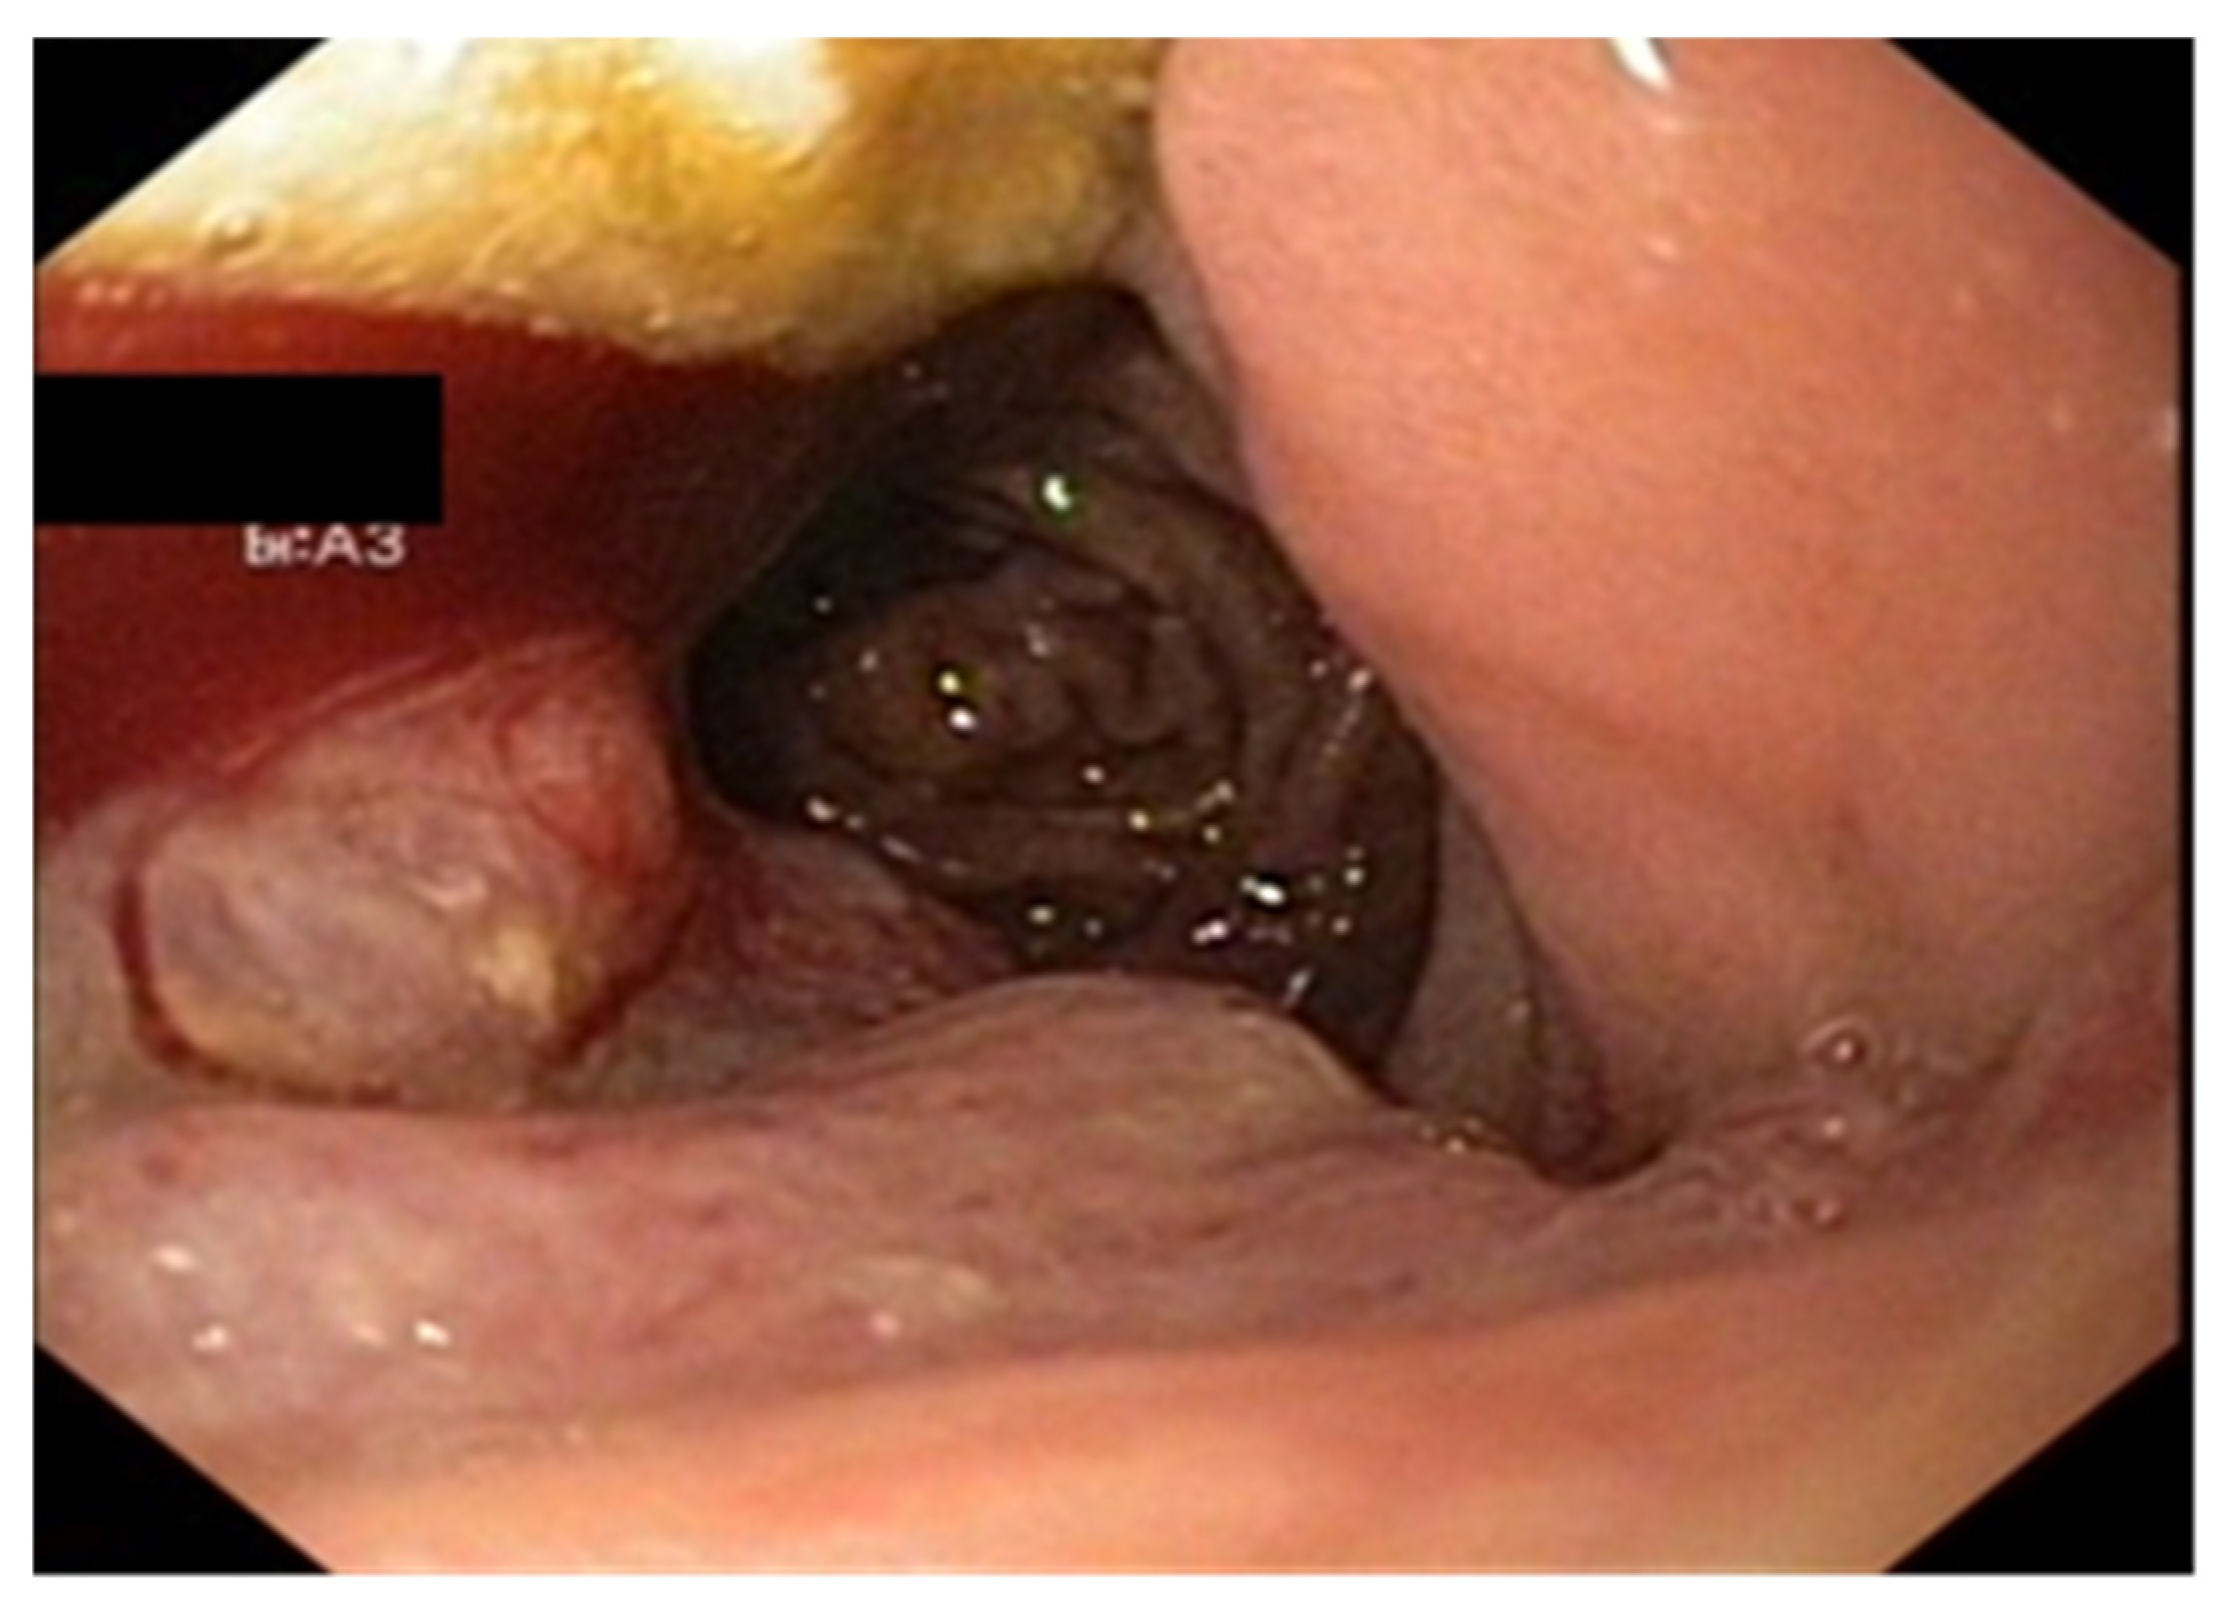

3.2. Treatment Particularities